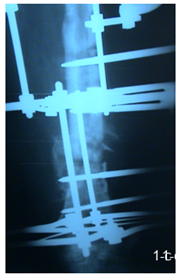

16 patients were operated by a single stage strategy with debridement of the fracture site through lateral approach with thorough excision of all infected tissues and necrotic bone and then fixation with ilizarov or uniplaner external fixation was done with acute shortening and compression at the fracture site in patients with bone defects of 2 cm or less, and use of autogenous cancellous bone graft was done in patients with bone defects more than 2 cm. (Figure 1 a, b & c).

Figure 1 a) Femoral infected non union. b) Postoperative by single stage, and c) After union.